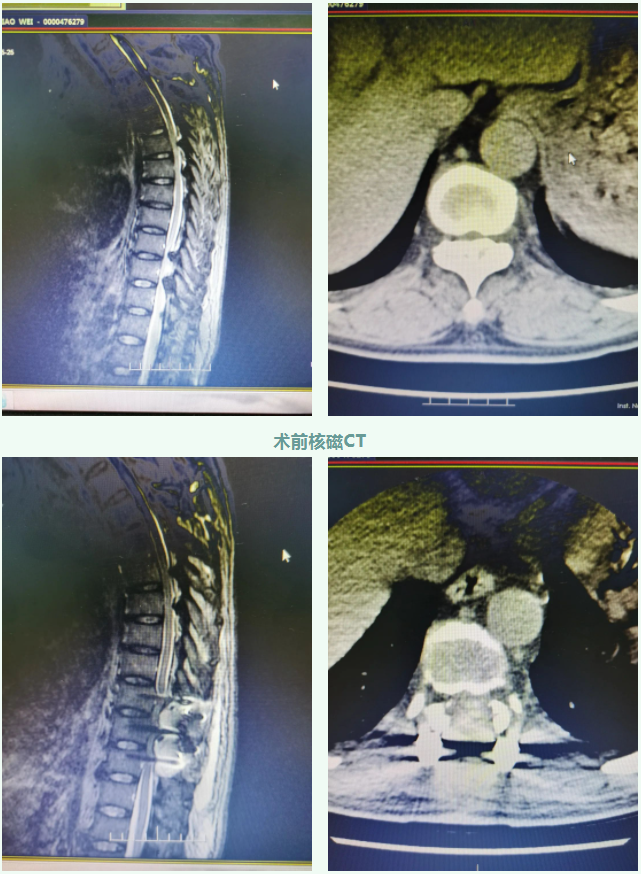

近日,佳木斯大學(xué)宏大醫(yī)院副院長(zhǎng)、骨科主任喬建民教授帶領(lǐng)的骨科團(tuán)隊(duì),成功為該患者實(shí)施長(zhǎng)節(jié)段胸椎黃韌帶骨化重度椎管狹窄切除、減壓、椎弓根螺釘內(nèi)固定術(shù)。(簡(jiǎn)單說(shuō)就是要把壓迫脊髓的致壓物去除,然后穩(wěn)定脊柱)

在喬建民院長(zhǎng)的組織下,對(duì)該患者完善相關(guān)檢查,診斷結(jié)果為“長(zhǎng)節(jié)段胸椎黃韌帶骨化癥、重度胸椎管狹窄、下肢不全癱”,收入我院骨科住院治療。例行手術(shù)迫在眉睫,患者家屬也表達(dá)了十分強(qiáng)烈的手術(shù)愿望,喬院長(zhǎng)向家屬堅(jiān)定地表示:“患者來(lái)到醫(yī)院是對(duì)我們的信任和肯定,我們一定不負(fù)所望,絕不會(huì)放棄,一定盡全力幫助患者解決病痛?!?/span>

胸椎管狹窄癥